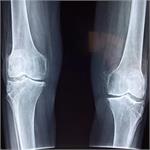

تیم محققان دانشگاه میسوری تصمیم گرفتند این موضوع را بررسی کنند که تشکیل غضروف در شرایط جاذبه ضعیف چگونه خواهد بود و شرایط بی‌وزنی مانند آنچه در ایستگاه فضایی بین‌المللی وجود دارد چه تاثیری بر ترمیم استخوانی خواهد داشت.

سلول‌های بنیادی غضروف که "کندراسیت"( chondrocytes) نام دارند برای ترمیم شکستگی‌های استخوانی ضروری هستند و بعلاوه بدن باید بتواند با تولید آنها استحکام استخوان‌ها را حفظ کند.

محققان دانشگاه میسوری با استفاده از تجهیزات ایجاد جاذبه صفر که متعلق به "سازمان فضایی آمریکا"(ناسا) است، موفق شدند رفتار سلول‌های بنیادی غضروف را در نبود جاذبه بررسی کرده و آن را با نحوه تکثیر این سلول‌ها در شرایط جاذبه زمین مقایسه کنند.

در طی این بررسی‌ها مشخص شد که این سلول‌ها روند تکاملی بسیار بهتری را در شرایط جاذبه زمین طی می‌کنند و استفاده از تجهیزاتی که جاذبه زمین را شبیه‌سازی می‌کنند می‌تواند در شرایط بی‌وزنی به رشد این سلول‌ها کمک کند هر چند که نتیجه مانند شرایط عادی نخواهد بود.

نتیجه این تحقیق نشان می‌دهد که زمین بهترین مکان برای درمان آسیب‌های استخوانی است و فضانوردان هر چقدر بتوانند بیشتر در شرایط مشابه زمین قرار بگیرند، بهتر می‌توانند از سلامتی خود محافظت کنند و بعلاوه این موضوع چالشی جدی برای زندگی در فضا محسوب می‌شود.